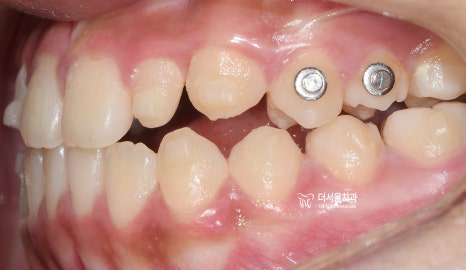

『구강 내 사진』

성장교정 이 필요한 이유는,

구강 내 사진에서도 뚜렷히 찾아볼 수 있습니다.

유치가 빠지면서 영구치아가 올라오고 있는

혼합치열기에서, 영구치가 올라올 수 있는

충분한 공간을 확보하면서

턱의 위치를 바로 잡는것이 핵심포인트입니다.

우선 여기서 봐야 될 큰 문제는

1) 절단교합(Edge to edge bite) 입니다.

윗니가 아랫니를 물고 있어야 되는데,

서로 절단연끼리 맞닿고 있죠.

그러면서, 성장교정 을 통해서

위턱의 크기를 발달시키며

아래턱은 억제시켜야 되는 상황입니다.